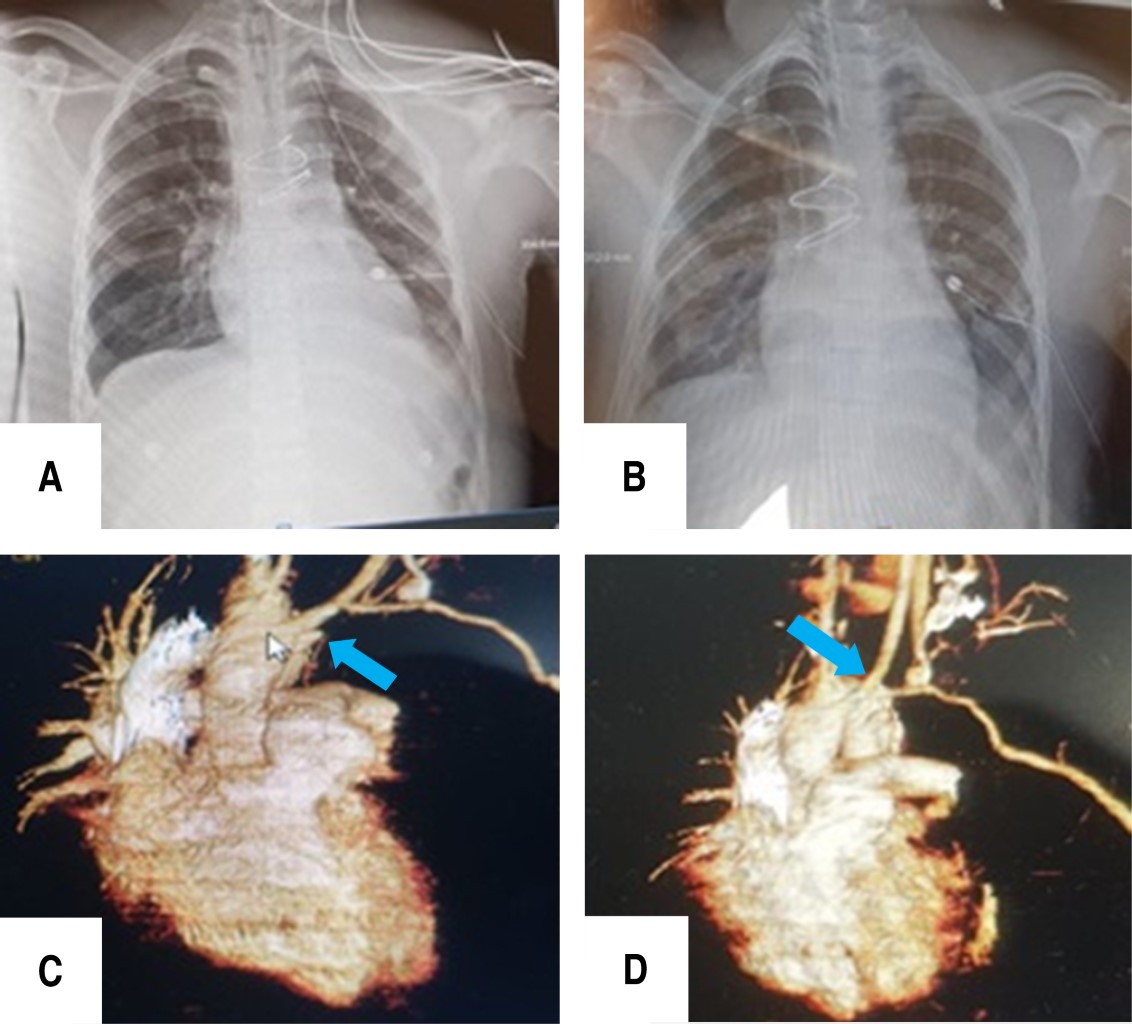

The patient was transferred to the recovery room with inotropic support of norepinephrine 8 mL/h, 1 gram of ceftriaxone IV every 8 hours and 500 mg of amikacin IV every 12 hours. The chest tube output was low. However, the X-ray showed moderate effusion, so repositioning a new chest tube in the intrapleural space was required (Figure 4A), which drained 700 mL of hematic fluid. The extrapleural chest tube was removed 28 hours later (Figure 4B).

Endotracheal extubation and intrapleural chest tube removal were performed within 72 hours postoperatively. The patient remained in the intensive care unit for 5 days and was then transferred to the ward, where was assessed by the neurosurgery and traumatology team for brachial plexus injury and humerus fracture, respectively. The patient was discharged from the hospital 15 days later. Since then, the patient has been in constant evaluation for 2 years, with a chest CT angiography that demonstrated graft patency (Figure 4C and D), although the brachial plexus injury has caused immobility and atrophy of the left shoulder and upper limb.